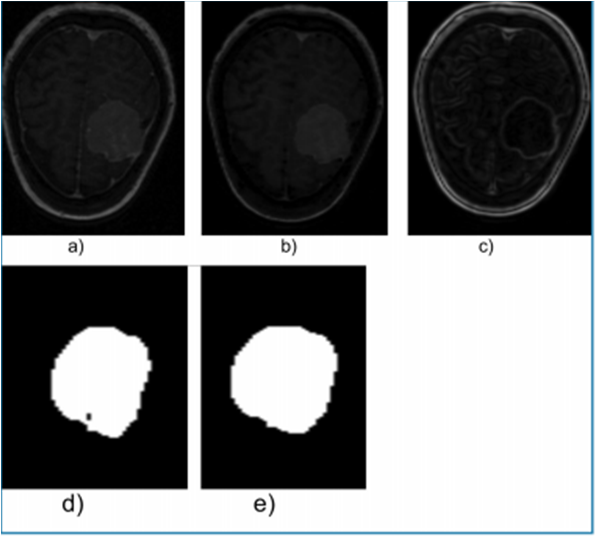

Figure 5, shows a 2-D view of both the original MGT and the processed versions after applying the proposed technique.